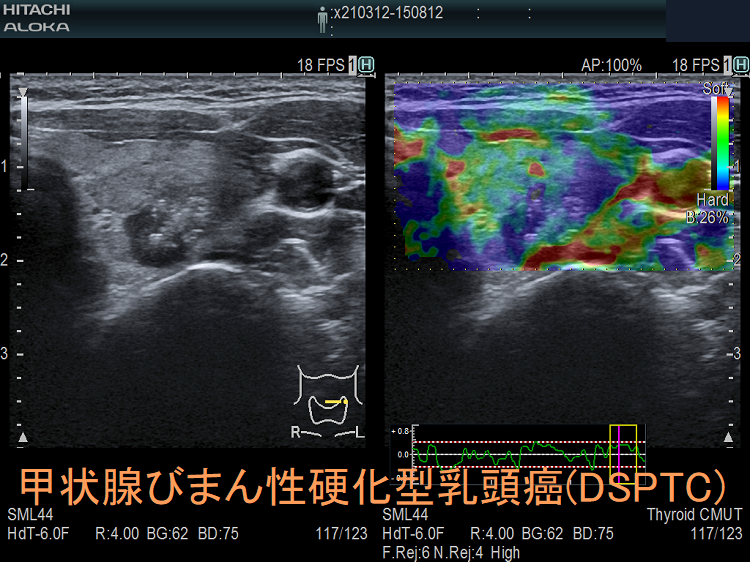

- 甲状腺超音波(エコー)検査において、不均一な病変で

等エコー(48.4%)、びまん性粒状石灰化(52.3%)、血流は乏しい(71.6%)

- 甲状腺エコーで、境界不明瞭で不均質な病変;等エコー(48.4%)、びまん性粒状石灰化(52.3%)、血流は乏しい(71.6%)[Clin Radiol. 2022 May;77(5):e356-e362.]

(エコー画像;Ultrasonography. 2017 Apr 36(2) 103–110.)